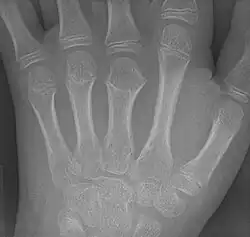

![]() Braquimetacarpia del tercer metacarpiano. | ||

Generalmente, cuando la braquimetacarpia es causa de la braquidactilia, la altura pequeña del metacarpo afectado es la que causa la falta de altura del dedo arriba del metacarpo, ya que en radiografias de dedos aparentemente cortos con braquimetacarpia, se puede observar que las falanges del dedo afectado son de altura normal, sin embargo, la altura del hueso metacarpo abajo de este es anormalmente corta, lo cual también afecta la "altura" del dedo, sin embargo, sí es posible que se presenten la braquimetacarpia y el braquifalangismo juntos.[3]